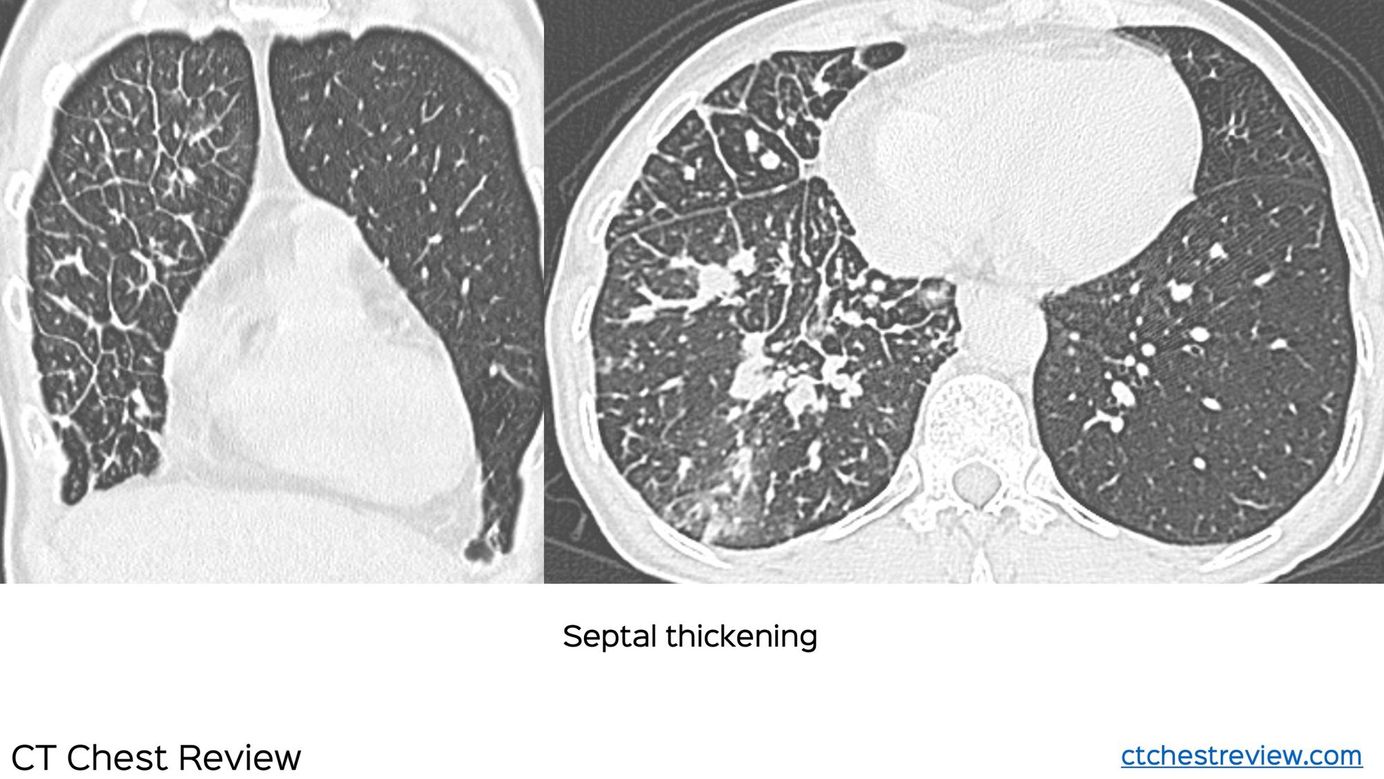

Case 4: Lymphangitis Carcinomatosis Members Public

70-years old lady with Ca breast, with progressive dyspnea. She had nodular septal thickening in the right lung, more in the right lower lobe with larger discrete nodules. These findings are characteristic of lymphangitis carcinomatosis